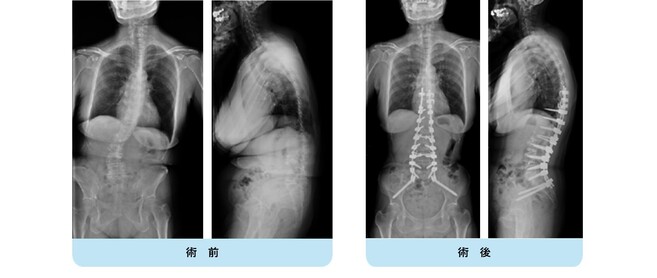

思春期特発性側弯症の全脊椎レントゲンで背骨がSの字に曲がっています。最も曲がっている箇所は52°で、成長終了後も高率にカーブが進行し続けます。50°前後の側弯であれば手術により80%以上まっすぐにすることができます。通常は70%程度の矯正率で良いとされていますが、本来出来るだけまっすぐする手術であり、バランスが損なわれるようなことがなければ我々は矯正率80%を目指しています。

この症例は術後の側弯角は8°で、矯正率は85%でした。また肩バランスも水平で保たれています。また注目すべきは腰の曲がりです。術前のレントゲンをみると腰にも側弯があるのが分かります。(黄色矢印)

腰椎の可動性を残すために、胸椎の側弯に絞って矯正固定を行い腰椎の側弯が引っ張られて改善することを期待しました。術後のレントゲンをみると金属が埋め込まれていない腰椎の側弯が大きく改善しているのが分かります。(黄色矢印)

この症例についても、横から見ると術前に右の背中が肋骨隆起(リブハンプ)により出っ張っています。(赤色矢印)

手術により側弯だけでなく回旋矯正、生理的胸椎後弯形成が成され、術後は右の背中の出っ張りがなくなり生理的な背中全体の丸みが復元されているのが分かります。(赤色矢印)

このように我々は側弯だけでなく、本来の生理的なshapeを取り戻すことを目標に治療を行っています。